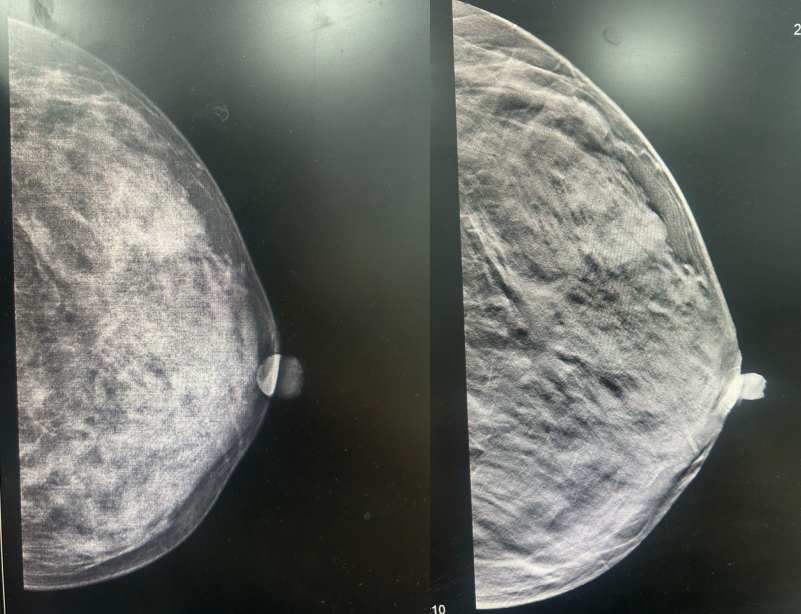

·乳腺彩超

2023-06-26彩色多普勒超声宽景成像+术前体表定位:

1、左乳4点钟方向实性肿块(乳腺Ca可能,BI-RADS 4C类),已体表定位,此次定位仅供手术医生参考。

2、双乳乳腺增生症。

3、双侧腋窝探及多个淋巴结。

图1.2023年6月24日乳腺彩超